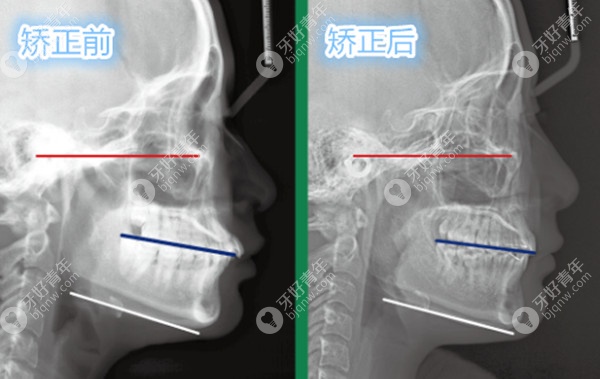

经过拍片,面诊医生告诉我,我的前牙覆合覆盖比较深,所以显得嘴突,而且从侧面看,我的颏唇沟也比较深,整体是属于低角下巴不后缩的症状,由于我口内的牙齿排列还算整齐,所以采用推磨牙的矫正方案。

后来在朋友的加油打气下,在一年后我还是如期复诊了,问了医生才知道推磨牙前期是看不到很大的变化。通过CT对比,让我重拾了信心,在医生的指导和自己的坚持下,终于在1年半后完成了矫正。